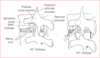

How does neurogenic claudication present?

- leg or buttock pain/weakness

- worse with prolonged standing

- worse with spinal extension and relieved with flexion

How does vascular claudication present?

- calf pain worse with activity (walking uphill, biking)

- skin changes (thin, shiny, hairless)

- diminished/absent pulses

Treatement for spinal stenosis

PT with directional preference assessment (flexion biased) or surgical decompression